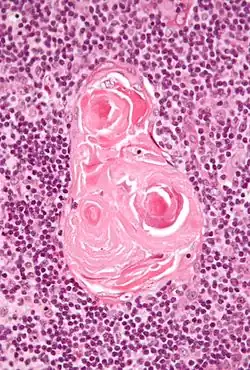

Клеточный состав мозгового вещества представлен опорными эпителиальными клетками, звездчатыми клетками, макрофагами. Имеются также выносящие лимфатические сосуды и тельца Гассаля.